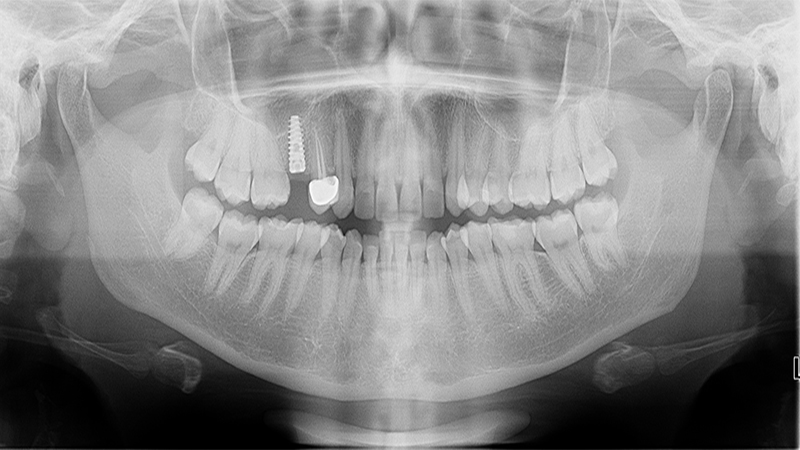

Implants

Implant Patients